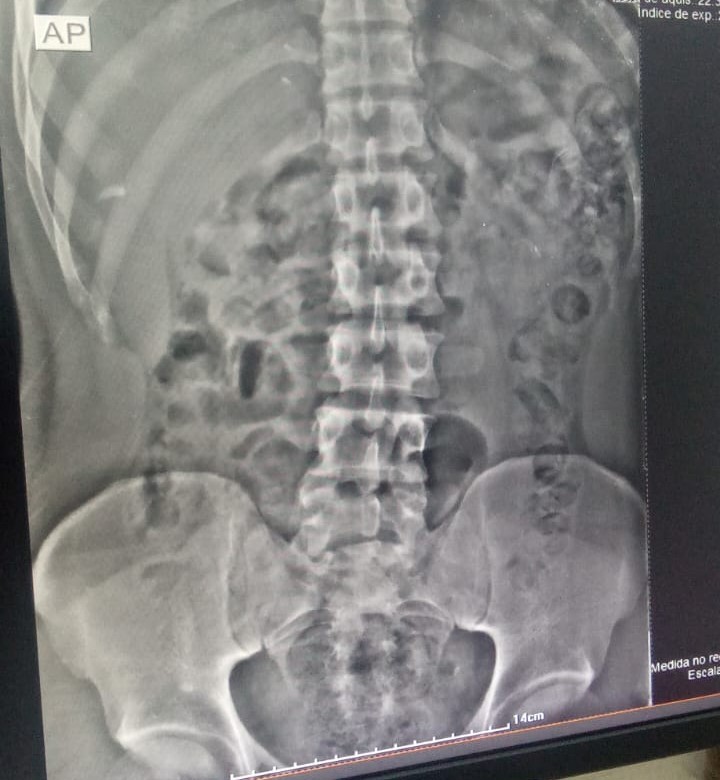

“Durante sua entrada na CPP, suspeitamos que havia algo errado. Na passagem pelo body scanner, vimos as substâncias ilícitas. Por isso, levamos o preso ao Hospital Regional de Formosa. A tomografia computadorizada sanou nossas dúvidas. Ele passou a madrugada expelindo as cápsulas dentro da cela, separado dos demais apenados”, explica o coordenador da 8ª Regional da Polícia Penal, Ayle Barbosa dos Reis Balbino.